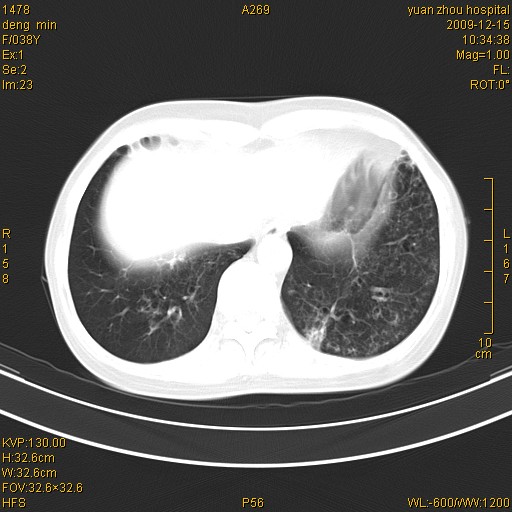

标题: CT23919:F38Y 咳嗽月余 [打印本页]

标题: CT23919:F38Y 咳嗽月余

右肺中下叶、左肺上叶舌段及左肺下叶支气管扩张合并感染。